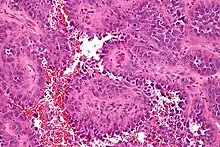

Fotografía microscópica de un angiosarcoma | ||